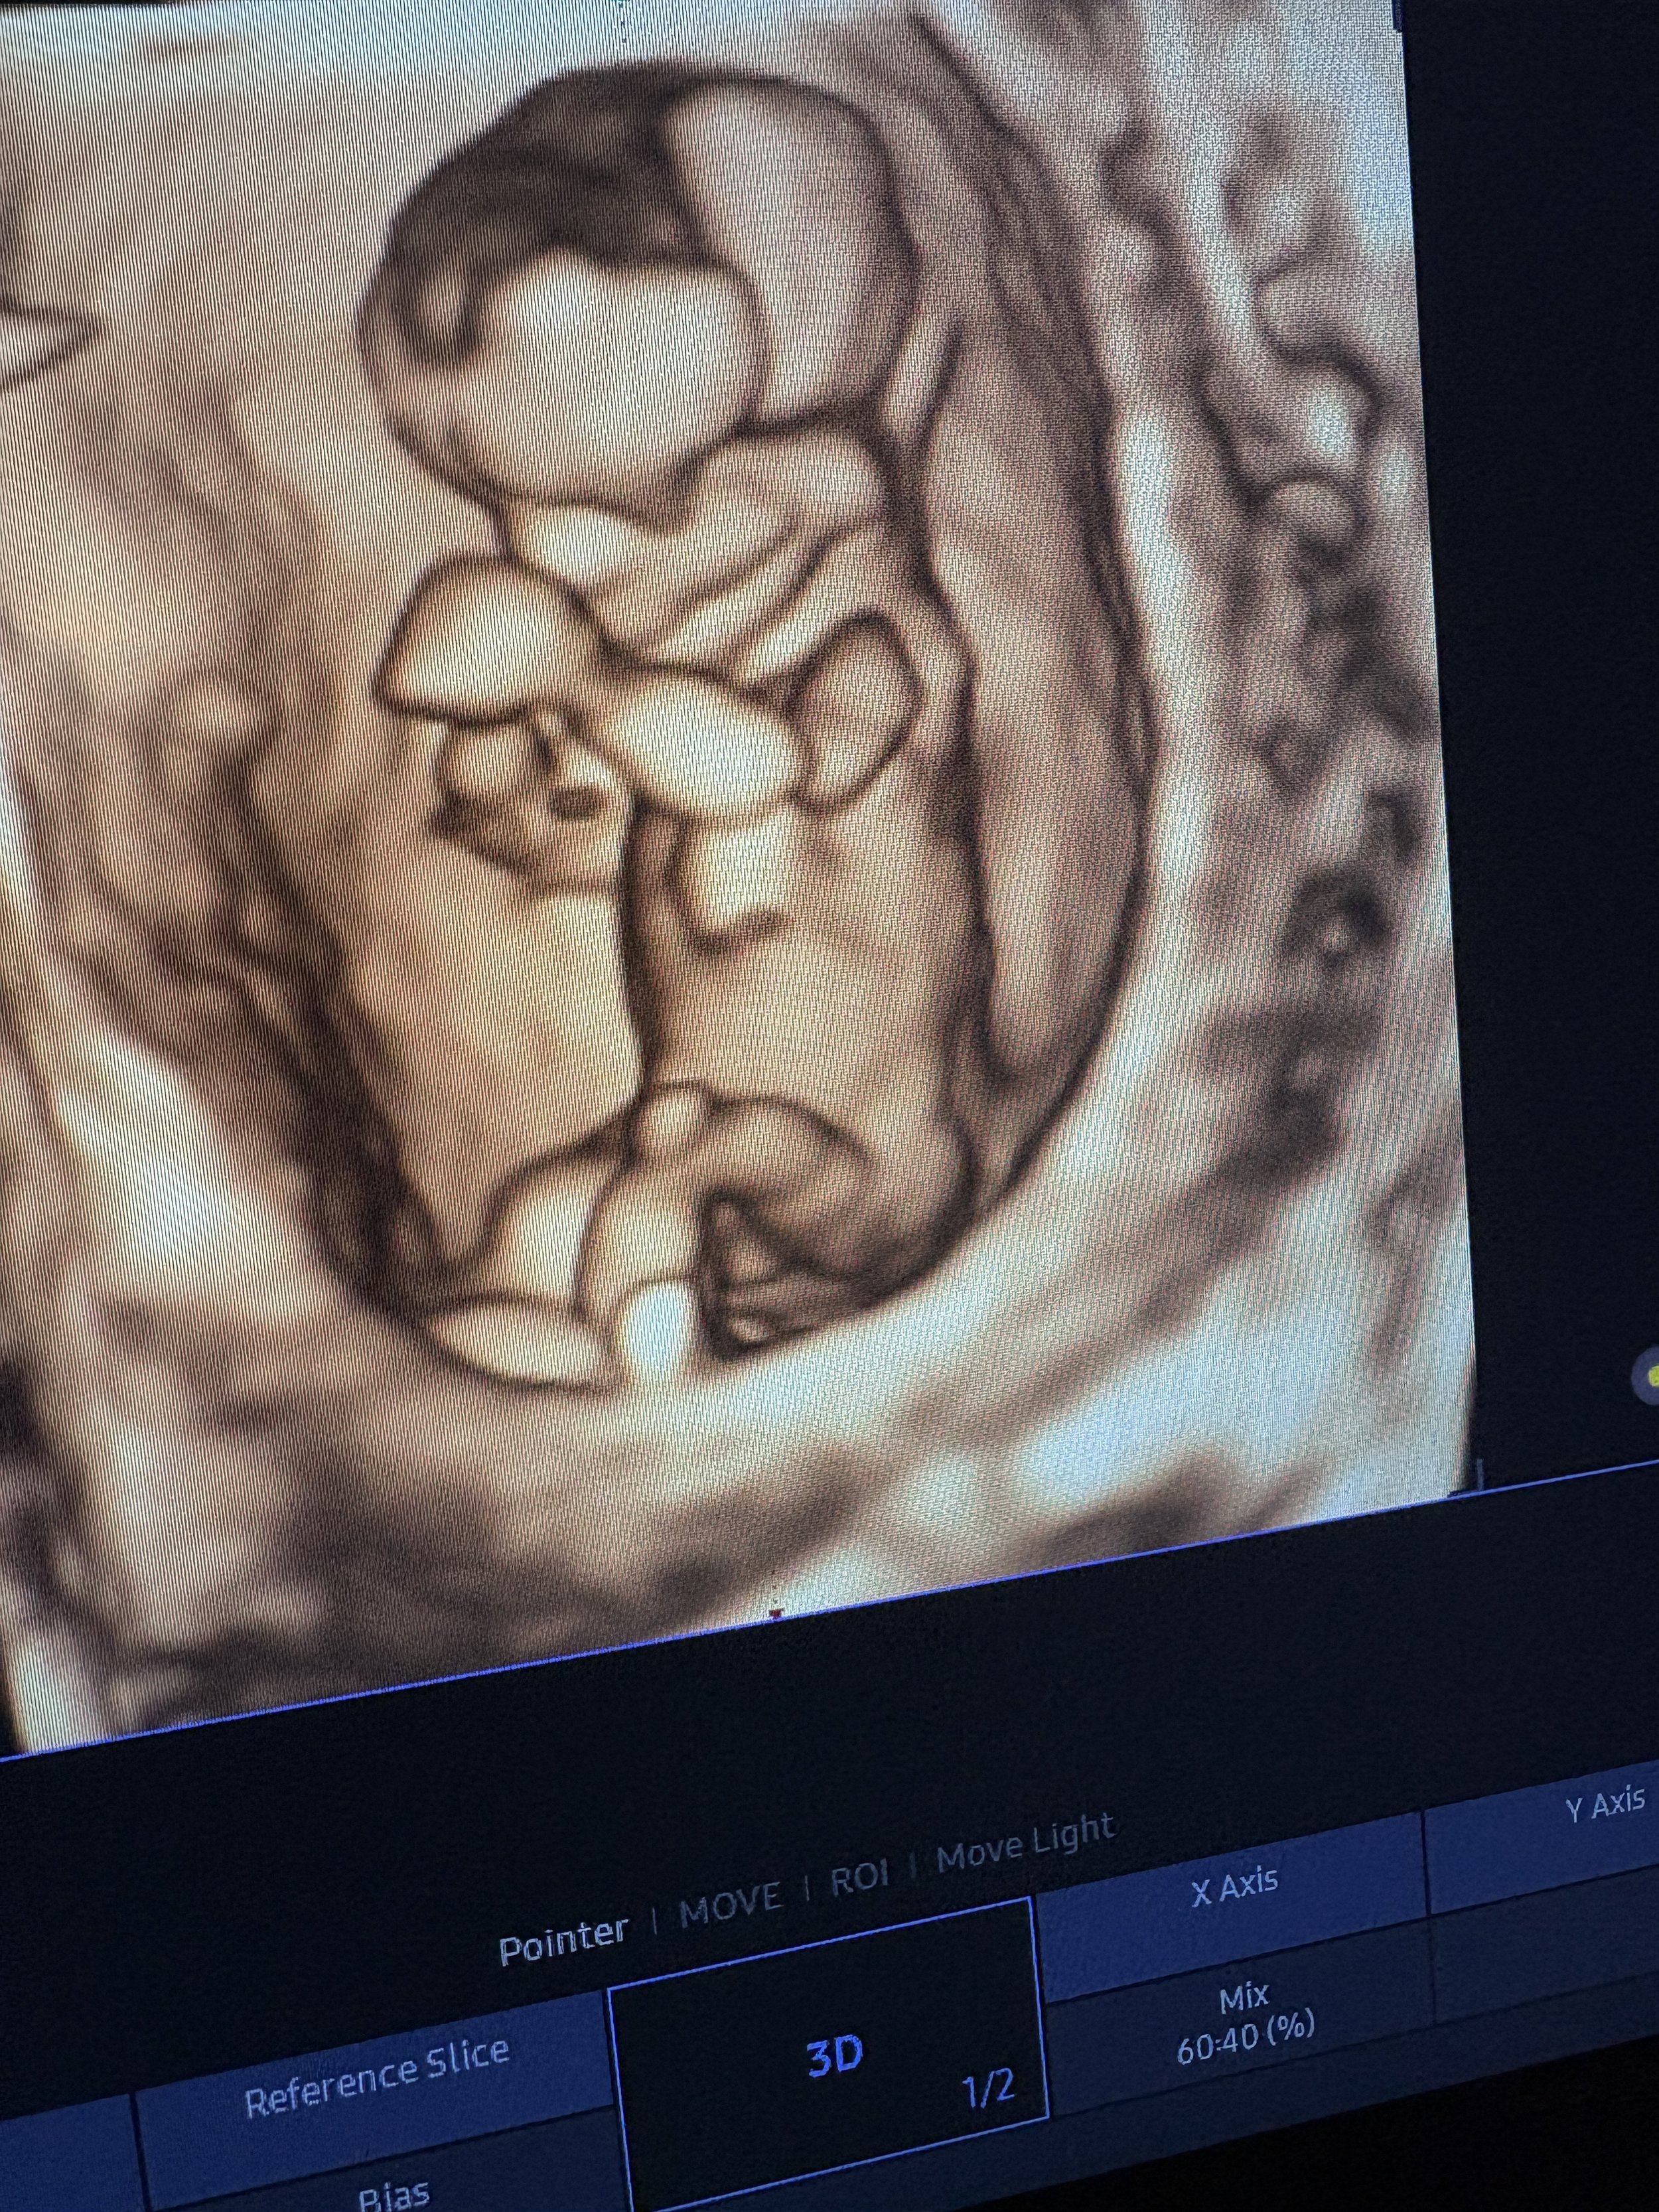

The Baby Gallery